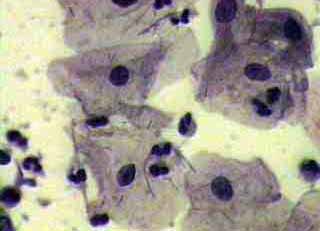

Πινακοθήκη κυτταρολογικών ευρημάτων ΙΙΙ

Οι πινακοθήκες κυτταρολογικών ευρημάτων, έχουν σαν στόχο να εμπλουτίσουν την κυτταρολογική εμπειρία σπουδαστών και ειδικευομένων, όπως ένας άτλαντας.

Παρουησιάζονται λοιπόν τυχαία ευρήματα, από το καθημερινό γυναικολογικό ιατρείο.